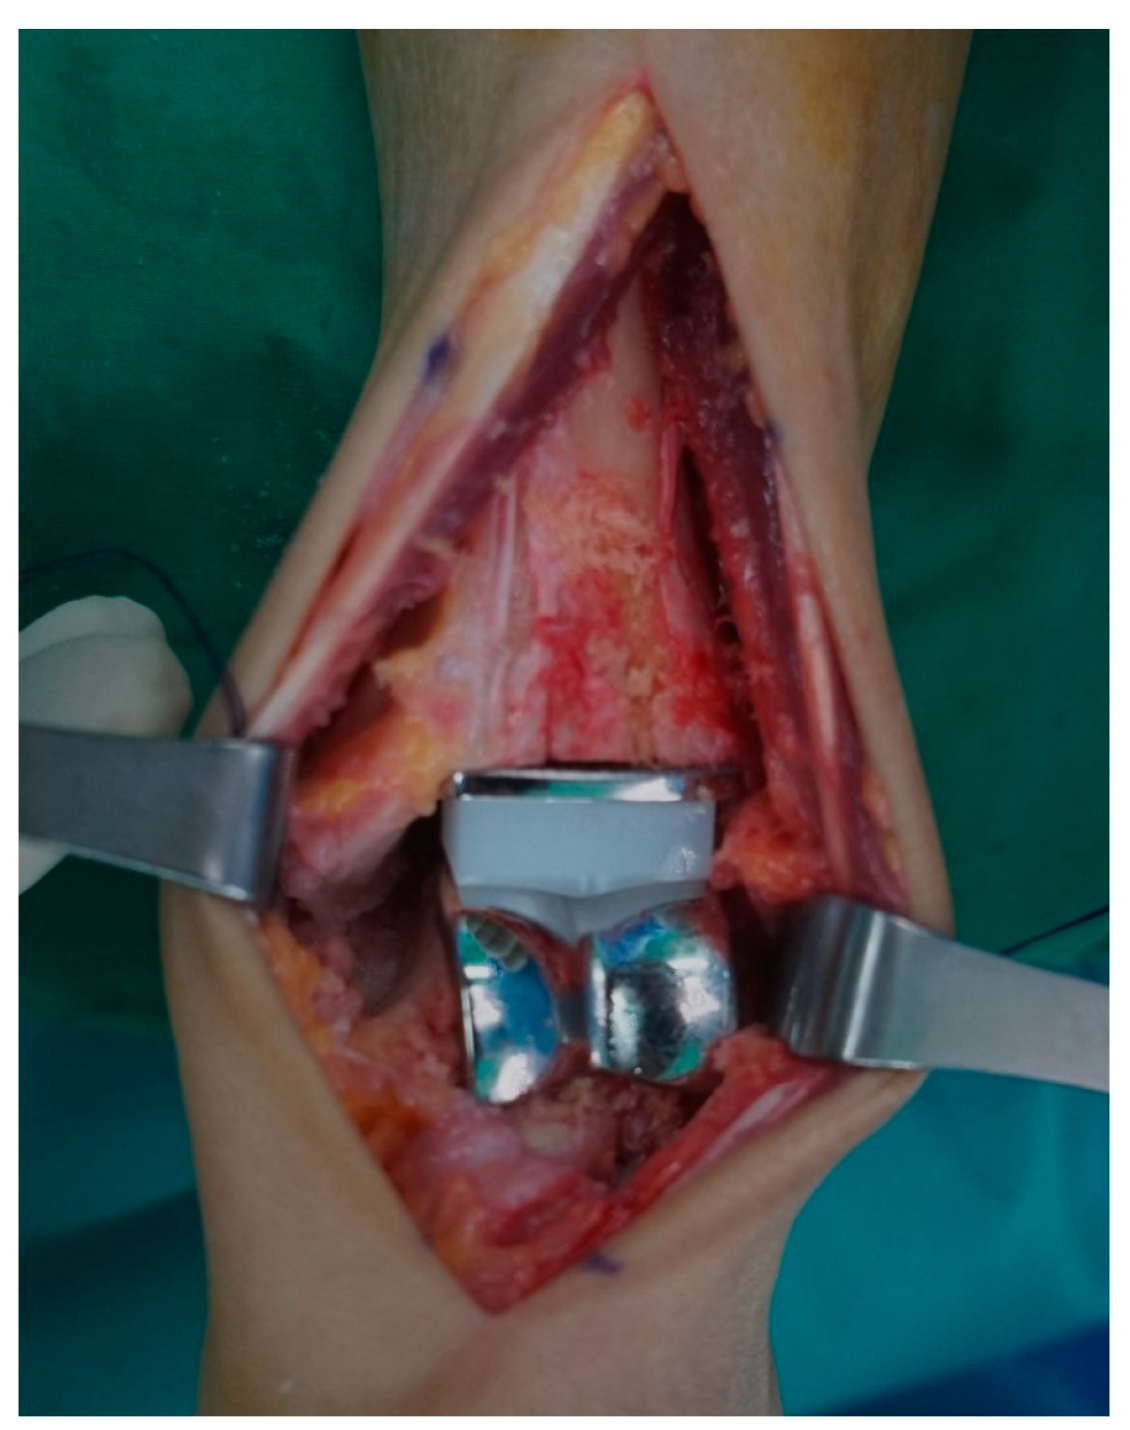

2.5. Postoperative Wound Assessment